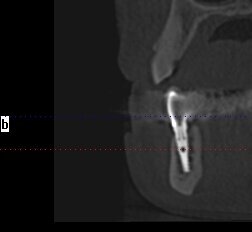

Wykonanie badania tomograficznego potwierdziło diagnozę o zaawansowanej nierokującej chorobie przyzębia (Ryc. 2). Po konsultacji została podjęta decyzja o ekstrakcji wszystkich zębów w żuchwie, natychmiastowym wprowadzeniu implantów z jednoczesną czasową odbudową protetyczna stałą mocowaną na wszczepionych implantach. Zlecono rutynowe badanie lekarskie i laboratoryjne.

Implanty zostały wprowadzone wg zasady przylegania w cieniu, tzn. wszczep musi na całej swojej długości mieć kontakt z którąś ze ścian zębodołu 1-2 mm subkrestalnie (Ryc. 4). W przypadku konieczności użycia membrany, musi ona mieć możliwość rozpostarcia się nad ubytkiem kostnym i implantem tak, aby odległość pomiędzy membraną a wszczepem nie była mniejsza niż 2 m (Ryc. 3). Wszczepy o

przygotowanej wcześniej protezie czasowej metodą bezpośrednią. Czasowe uzupełnienie protetyczne osadzono, używając cementu tymczasowego (Ryc. 5 i 6). Zlecono wykonanie zdjęcia techniką CBCT (Ryc. 7). Wizytę kontrolną wyznaczono następnego dnia, a szwy zostały usunięte po 10 dniach.

zlecono też wykonanie kontrolnego zdjęcia CBCT i następnego po 12 miesiącach (Ryc. 10 i 11).

W kwietniu 2017 r. został wykonany status periodontologiczny pozostałego uzębienia i wszczepionych implantów (Ryc. 12) i ponowne badanie CBCT (Ryc. 13- 15). Stan 3 lata po zabiegu przedstawiono na rycinach 16-18. Pacjentka jest ujęta w programie Recall w cyklu 6-miesięcznym od dnia wykonania zabiegu.